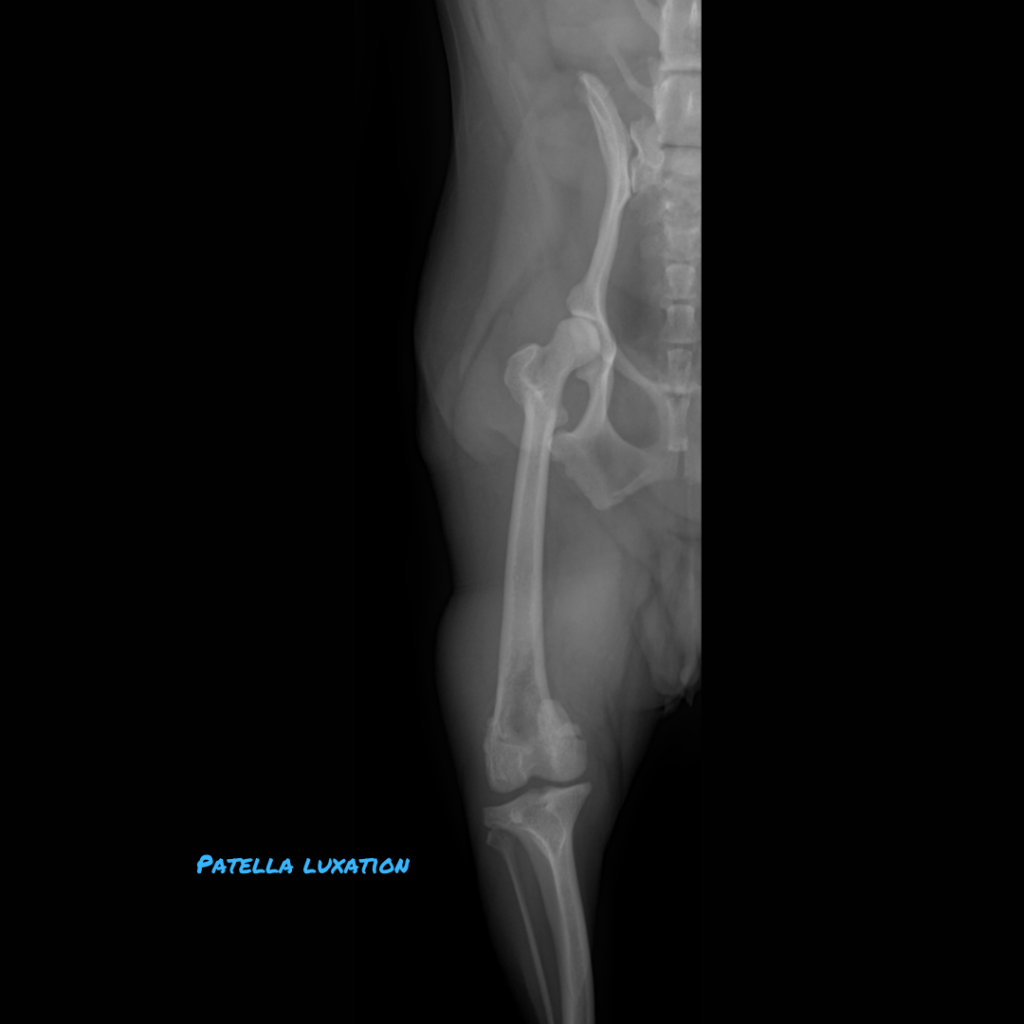

Patellar luxation occurs when the kneecap slips out of its groove, shifting medially or laterally. The patella is embedded within the tendon that connects the quadriceps muscle to the tibial tuberosity, assisting in knee straightening. The patella shields the tendon as it glides over the end of the thigh bone.

Most luxations are medial and caused by anatomic abnormalities, although traumatic luxations can also occur. Anatomic factors can also cause lateral luxation, usually in young animals.